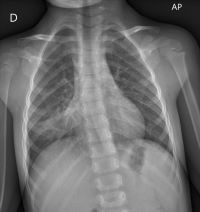

Paciente de 3 años y 9 meses con adenopatías cervicales bilaterales múltiples de predominio izquierdo de 48 horas de evolución, la mayor de ellas de 3,5-4 cm, dolorosas, duras y adheridas sin aumento de calor local ni hiperemia cutánea. Presenta palidez cutánea. El resto de la exploración física, incluida la auscultación pulmonar, es normal. Temperatura axilar máxima de hasta 38 °C de 7 días de evolución con astenia. Los primeros dos días tenía tos irritativa que cede. Analítica sanguínea: 13 450 leucocitos, 9360 neutrófilos. PCR 75,4 mg/l, VSG 44 mm, serologías de toxoplasma, virus de Ebstein Barr y citomegalovirus negativas. Ante los hallazgos, se completa estudio con radiografía de tórax, donde se objetiva neumonía (Figura 1) y serología Mycoplasma pneumoniae. Inmunoglobulina M positiva. Se trata con azitromicina oral, presentando desaparición de adenopatías y fiebre a las 48 horas del inicio del tratamiento.

Figura 1. Radiografía de tórax